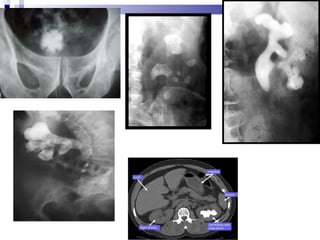

DIAGNOSIS

 History collection ,physical examination

 Urine analysis ,blood chemistries

 Stone analysis

 Flat radiographic plate of abdomen

 Ultrasonography

 Intravenous pyelogram

 CT scan

 Cystoscopy

DIAGNOSIS  History collection,physical examination  Urine analysis ,blood chemistries  Stone analysis  Flat radiographic plate of abdomen  Ultrasonography  Intravenous pyelogram  CT scan  Cystoscopy